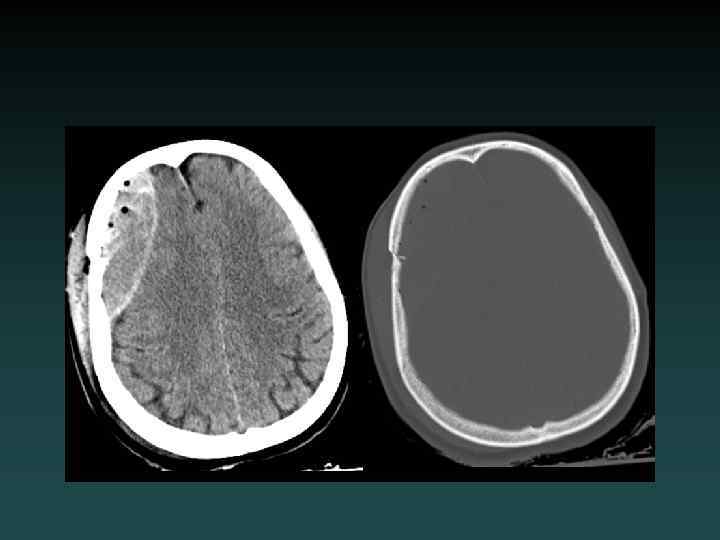

Acute Subdural Hematoma • Injury to bridging vessel – Venous • Crescent shaped • May cross sutures – Does not cross falx or tentorium • Does not enter sulci • Watch for: – MASS EFFECT – SLOW EXPANSION

Chronic Subdural Hematoma • HYPODENSE – (blood degradation) • MIXED – (Acute-on-chronic)

Isodense Subdural Hematoma • ISODENSE – Coagulopathy – Anemia – Evolution of blood products • Look for: – Sulcal Effacement – Subtle Mass Effect